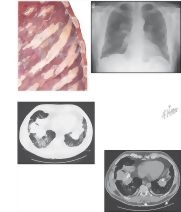

Asbestosis